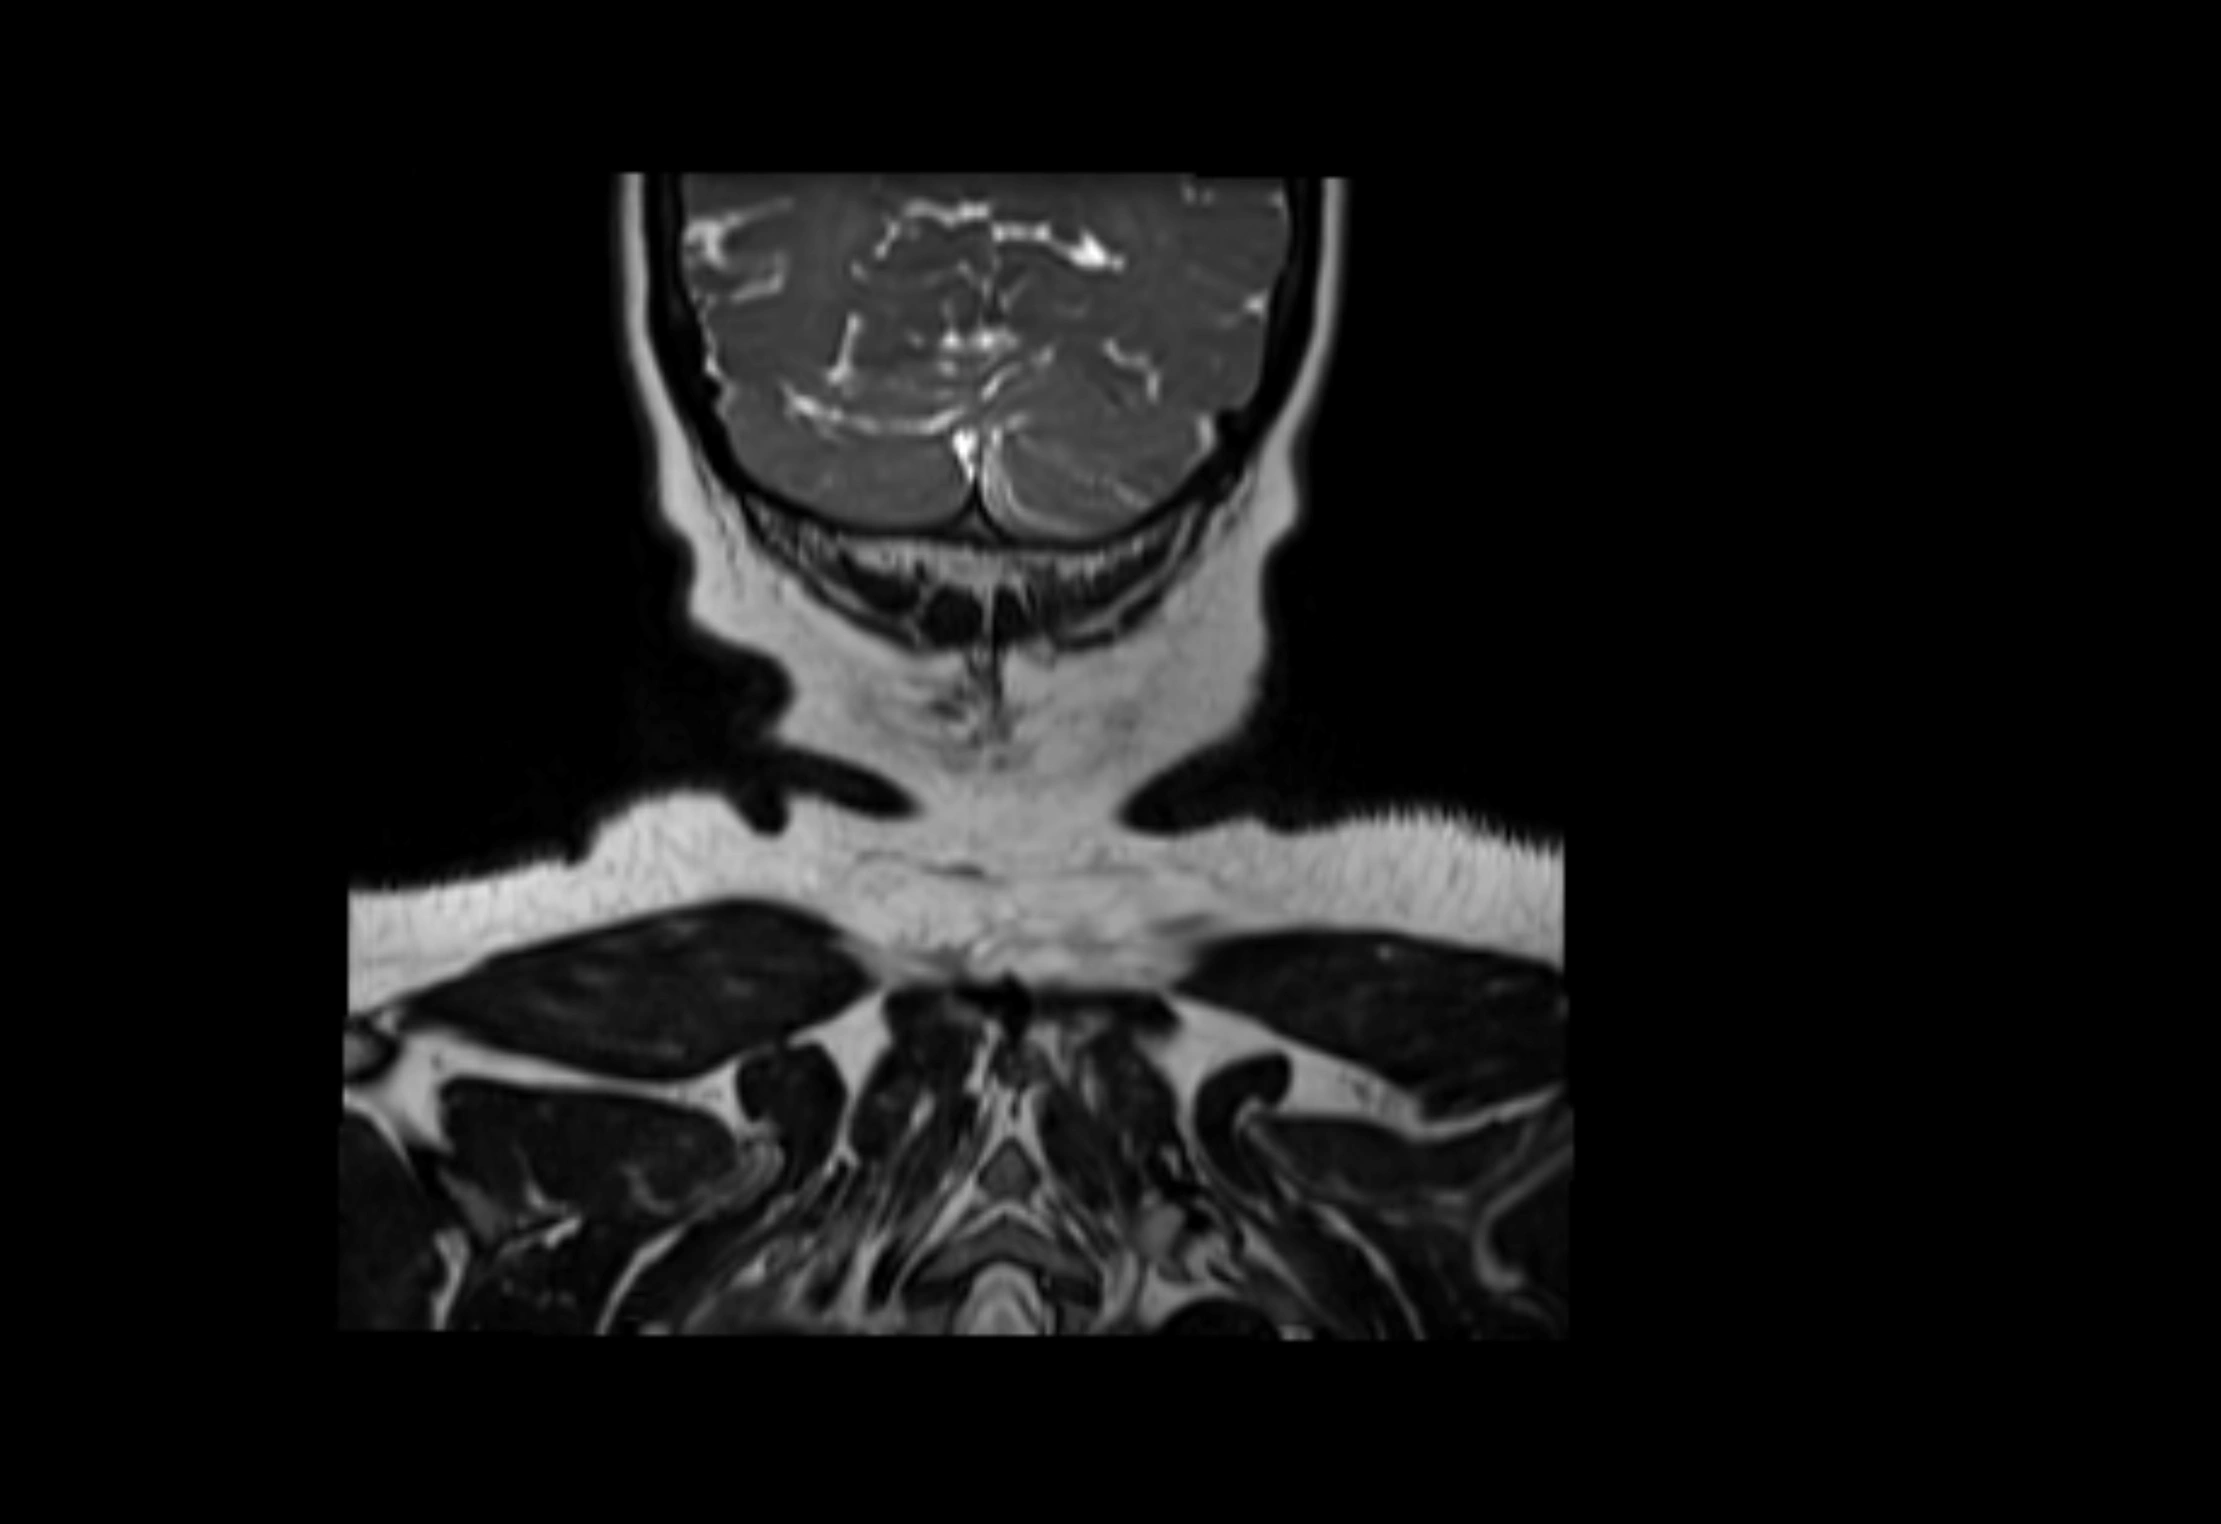

MRI images

image